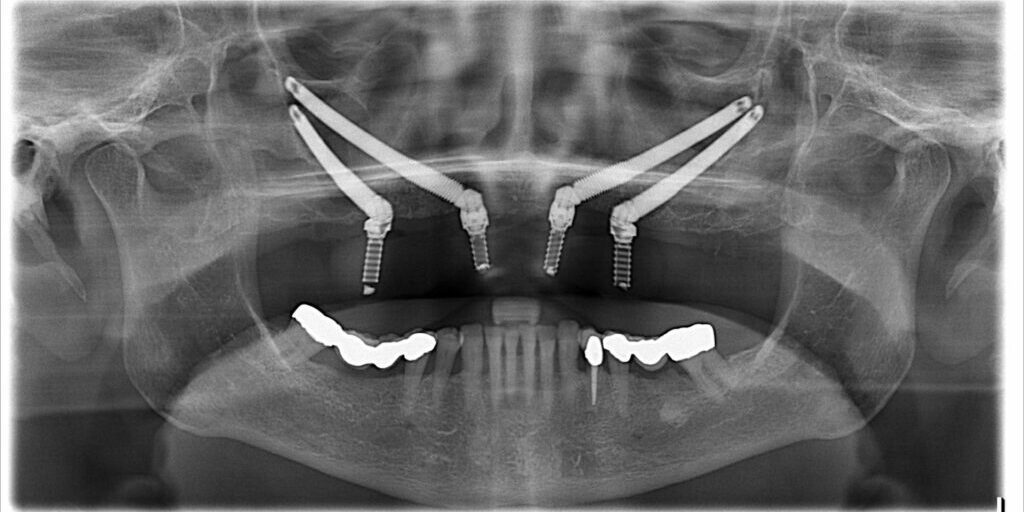

Zygomatic implants find their anchor in the zygoma or cheekbone, offering a robust foundation for prosthetic rehabilitation in cases of compromised maxillary bone. Unlike conventional implants, which rely on the jawbone, zygomatic implants break free from limitations, providing a lifeline for individuals previously deemed unsuitable for implant-supported prosthetics due to inadequate bone volume or quality.

The journey into zygomatic implants begins with a meticulous exploration of the patient’s anatomy, functionality, and aesthetics. Advanced imaging, such as cone-beam computed tomography (CBCT), serves as a critical tool for surgical planning, ensuring that implant placement not only offers a sturdy base but also aligns harmoniously with the patient’s functional and aesthetic goals.

Delving deeper into the world of zygomatic implants reveals a realm where prosthetic rehabilitation becomes attainable for those with severe maxillary atrophy or following tumor resection. Although technically demanding, the procedure, performed under general anesthesia, offers patients the opportunity to regain functional and aesthetically pleasing dentition.